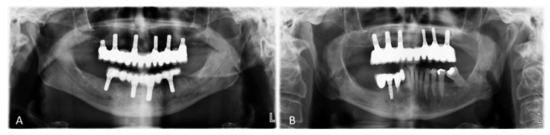

| Male | Female | Mean Age | Smokers | Maxilla | Bone Type 1 I, II, III, IV | Insertion Torque 1 (Ncm) | Antagonist 1 | |

|---|---|---|---|---|---|---|---|---|

| 3 | 3 | 59.8 | 4 out of 6 | 16 and 26 | Type I: 0 Type II: 0 Type III: 6 Type IV: 6 | <15: 0 15 < x< 35: 6 ≥35: 6 | ND: 2 FDP: 2 OD: 0 Mix: 8 | |

| STANDARD | 3 | 2 | 60.8 | 2 out of 5 | 16 and 26 | Type I: 0 Type II: 0 Type III: 6 Type IV: 4 | <15: 0 15 < x < 35: 6 ≥35: 4 | ND: 2 FDP: 0 OD: 2 Mix: 6 |